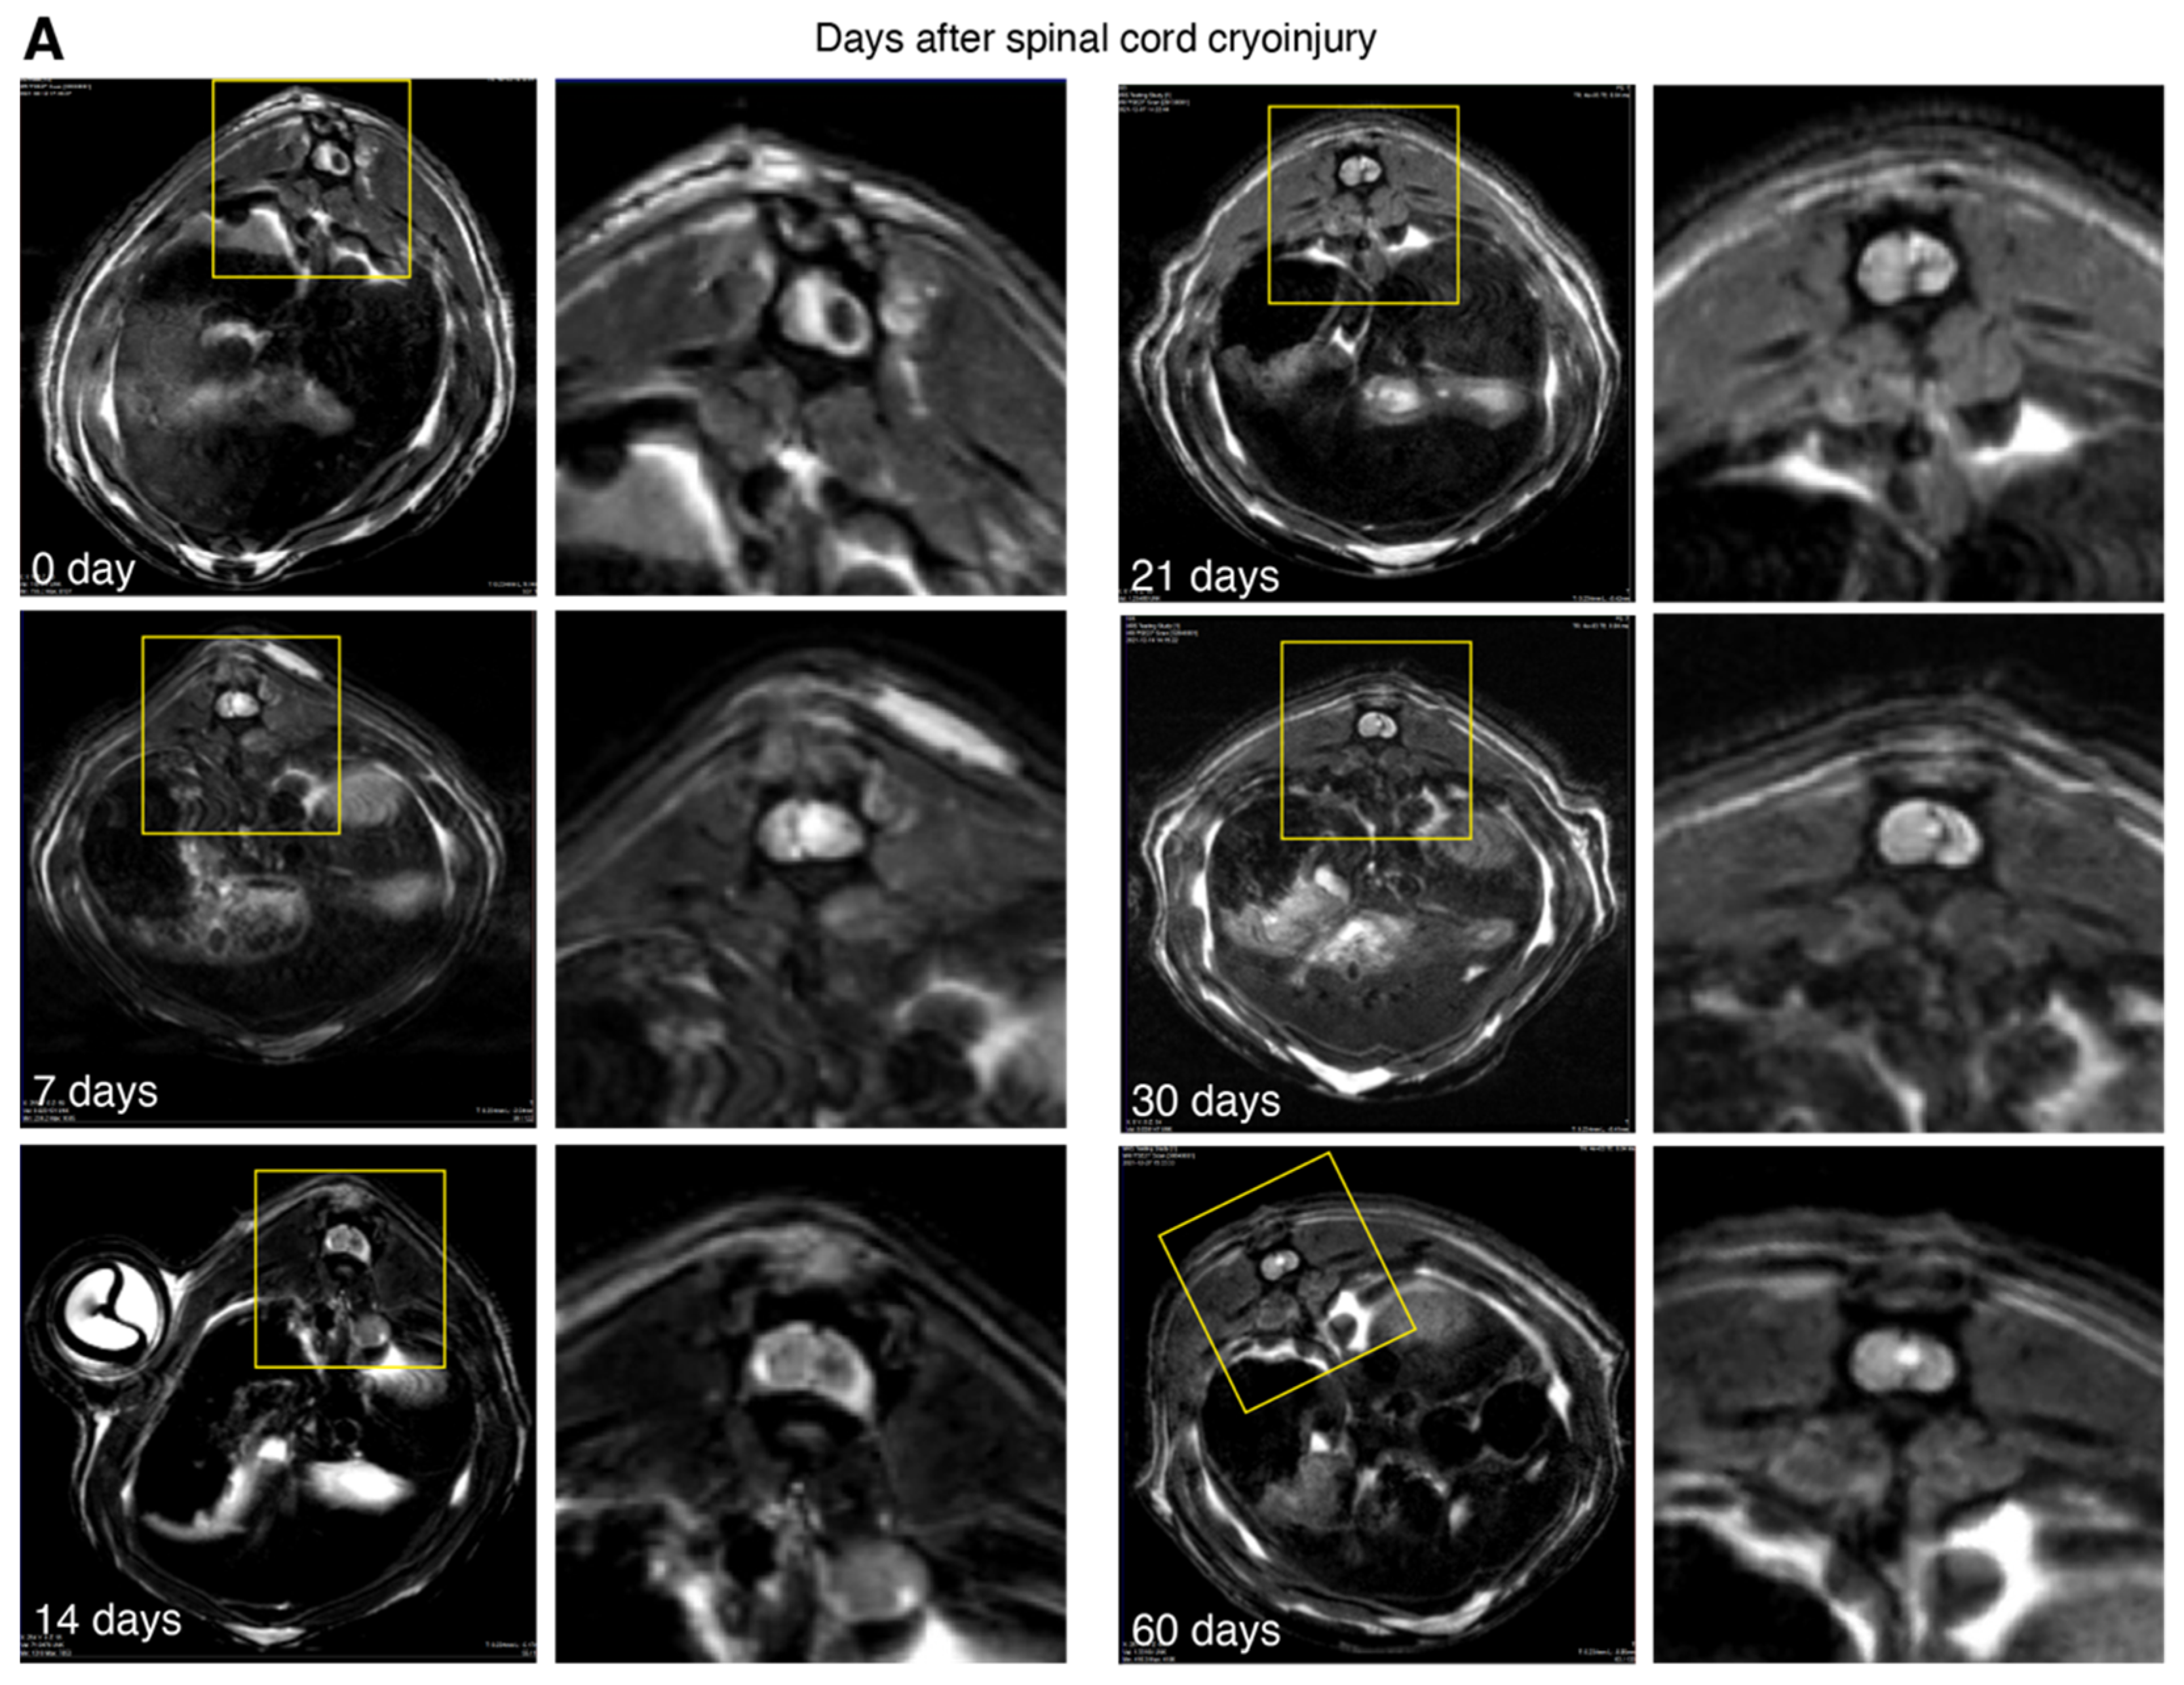

3.3. Magnetic Resonance Imaging of the Spinal Cord Cryoinjury